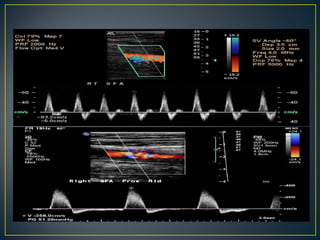

• Doppler ultrasound

• Duplex imaging

• Effective method of predicting the location and

severity of arterial disease in the lower

extremities

• Can distinguish between stenoses and

occlusions.

• ideal for predicting access sites for intervention,

and can detect iatrogenic arterial injury after

intervention.

• Effective methodof predicting the location and severity of arterial disease in the lower extremities • Can distinguish between stenoses and occlusions. • ideal for predicting access sites for intervention, and can detect iatrogenic arterial injury after intervention.